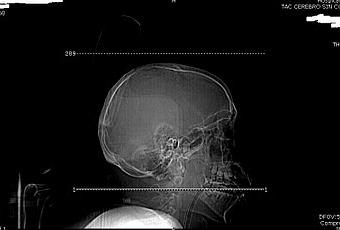

Hoy pudimos conocer por medio del Sofware Synapse,las placas de Rayos y scaner tomado al paciente que confirman el daño cerebral

Puedes ver las placas más abajo.